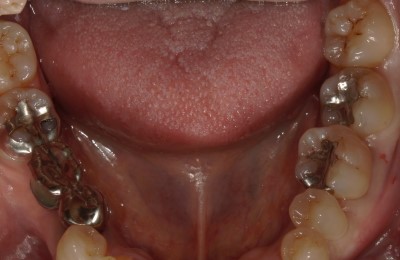

CASE03ダイレクトボンディング

Before

After

| 主訴 | できるだけ歯を削らずに銀歯を白くしたい。 |

|---|---|

| 治療方法 | 銀歯を除去した後、ダイレクトボンディング法によりコンポジットレジンを用いて修復した。 |

| 治療期間 | 1回 |

| リスク | 長年使用することによる着色。咬合圧が強い場合破折することがある。 |

| 費用 | 55,000円×2(税込み) |